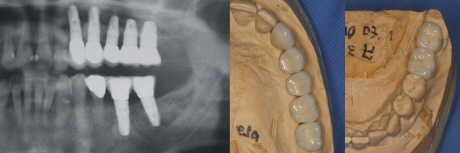

Das rechte Bild zeigt die Kronen auf dem zahntechnischen Meistermodell.

Einzementierte Kronen

Nach Anprobe werden die Kronen auf den Implantataufbau einzementiert.

Die fehlenden Zähne sind ästhetisch und funktionell im Ganzen (Wurzel und Krone) wieder hergestellt.